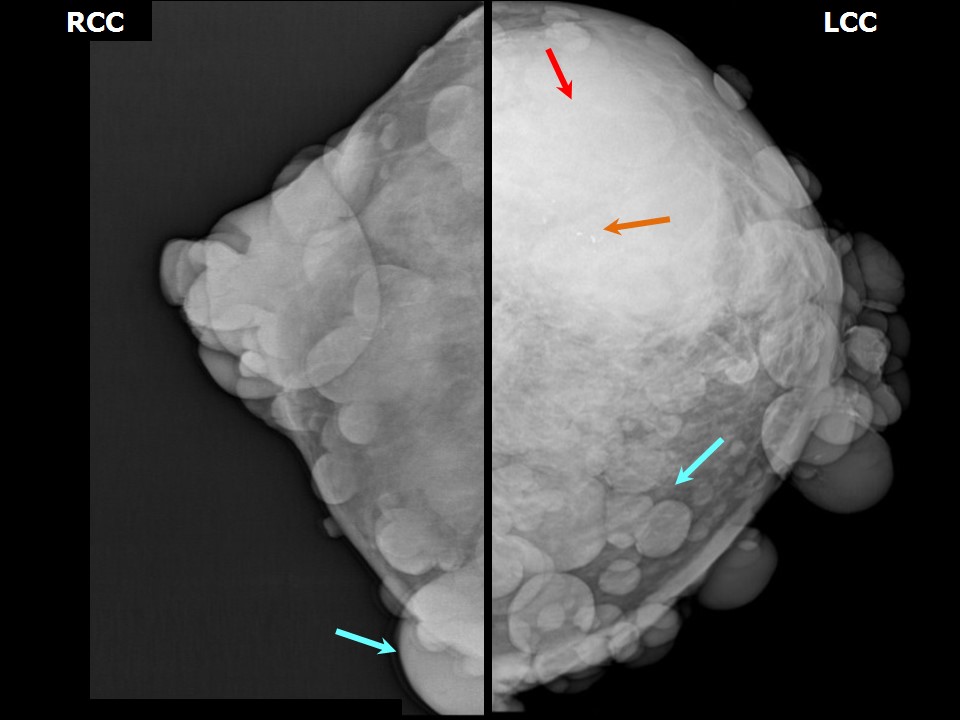

Феномен гипердиагностики в маммографии: примеры и иллюстрации

Раздел: Образы вокруг